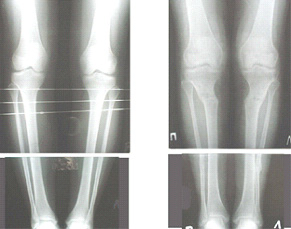

Картинки - в приложении.Будут вопросы - готов ответить.

Вот ещё картинки, которые отправлял в Ортопод. Коррекция кривизны и удлинение на 3 см.